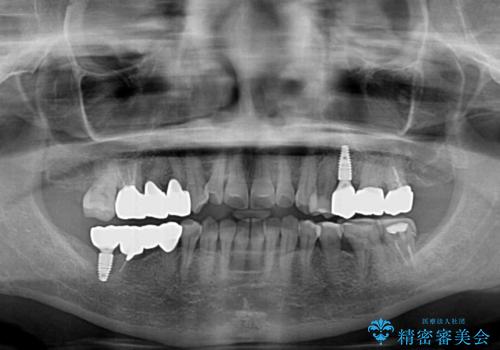

仮歯に置き換えた時点で歯肉からの出血は収まり、不快感が改善されました。

右下は、残存歯の状態があまり良くなかったため、今後抜歯となったことを想定して、最後臼歯のインプラントを決定しました。